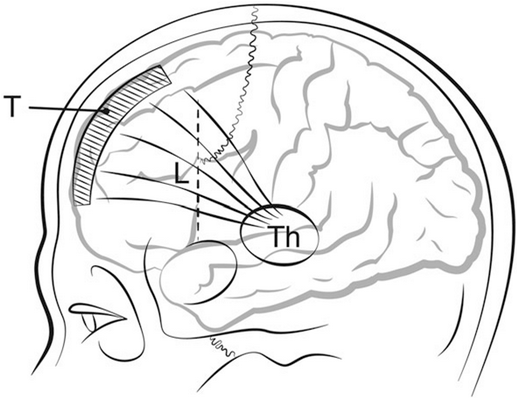

Открытие Пейпецом (1937 г.) основного круга эмоциональной регуляции а также других анатомических взаимосвязей в ЦНС позволили пионерам селективной психохирургии разработать гораздо менее травматичные для мозга способы лечения.

Стереотаксическая нейрохирургия вдет свою историю с аппаратов Д. Н. Зернова и Горслея - Кларка, созданных на рубеже 19-20 столетий, однако только вариант стереотаксической системы Ричардсона-Вайсса (1947 г.) натолкнул различных исследователей на мысль о применении ее для деструкции весьма небольших структур круга Пейпеца [1,2].

Хью Кэйрнс и Г. Т. Баллантин разрабатывают переднюю цингулотомию в 1948 г.

В 1961 г. Джеффри Найт предлагает устанавливать стереотаксически 3-5 иттриевых стержней 1х7 мм билатерально в белом веществе впереди и ниже головки хвостатого ядра для лечения тревожных и депрессивных расстройств и ОКР, процедура была названа им субкаудатная трактотомия.

Жан Талайрак разрабатывает переднюю капсулотомию в 1949 г.

Десмонд Келли и Алан Ричардсон разрабатывают лимбическую лейкотомию в 1973 г.: лимбическая лейкотомия по сути является сочетанием передней цингулотомии и субкаудатной трактотомии и предназначалась в первую очередь для избегания повторных операций по поводу рецедивов депрессии и ОКР. Наиболее перспективным методом лечения на сегодня является не деструкция, а стимуляция различных анатомических структур, часть из которых является целью и для деструкции.